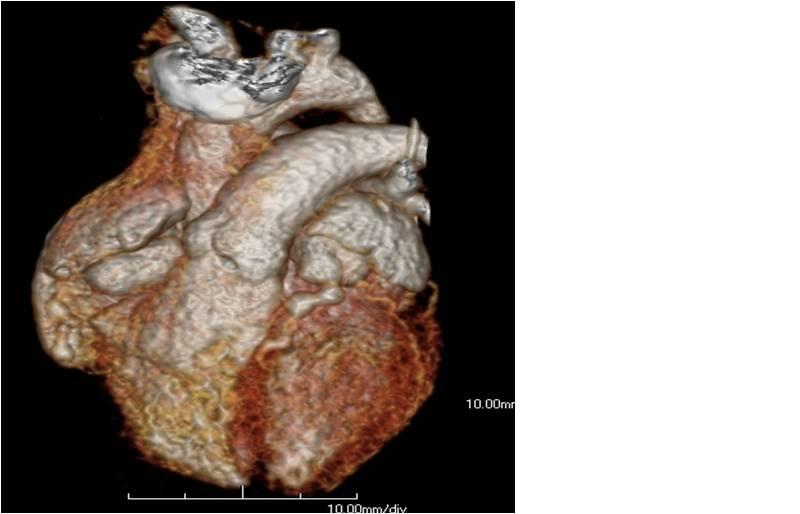

M/60 C.C. Atypical chest pain (since 2months) / Diabetes + / HR at MDCT scan: 70-75 bpm.

CHARY DURAIKANNU, VRR Diagnostics, INDIA

HIT : 82